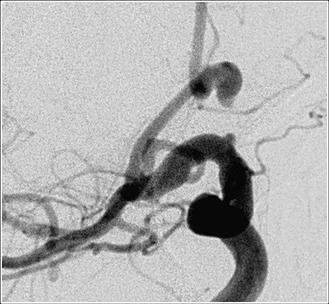

An aneurysm that has not bled is typically discovered on a CT or MRI scan (Figure 2) that is being done for evaluation of problems that may be unrelated to the aneurysm. If an aneurysm is discovered in this manner it is referred to as an 'incidental aneurysm.'

If an aneurysm bleeds, then CT scan is typically done to confirm the bleed and for evaluation of the aneurysm the best diagnostic tool available currently is a catheter angiogram.